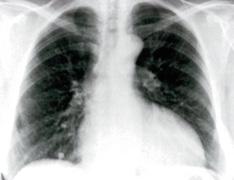

Derrame pericárdico severo da imagen en botellón en la radiografía de tórax. (ENAM EXTRA 2021)

Radiología:

Cardiomegalia

Signos de congestión pulmonar.

Radiografía: cardiomegalia con hipertensión venosa pulmonar